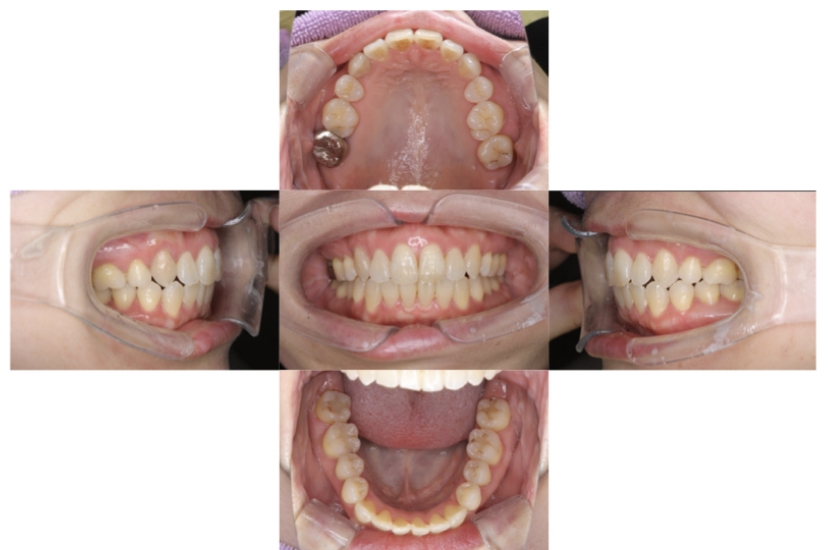

症例1

上顎前突、叢生

抜歯

ブラケット矯正

上下顎叢生、上顎前突(出っ歯、上下の前歯のガタガタ)のケースです。

装置はラビアル(上下表側)で、上顎の小臼歯を2本抜歯を行っています。抜歯したスペースを使って、上の前歯の後方移動と叢生(ガタガタ)と出っ歯の改善を行っています。下は歯と歯の間にIPR(隣接面削合)を行い、スペースを確保し、叢生の改善を行っています。

主訴 前歯のガタガタと出っ歯が気になる。

年齢・性別 47歳 女性

お住まいの地域 神奈川県川崎市

治療方針 抜歯スペースおよびIPRを利用して上前歯の叢生(ガタガタ)の改善

抜歯部位 上顎左右第一小臼歯

使用装置 ラビアル(上下表側)、顎間ゴム

治療期間 2年0か月

治療回数 15回

リテーナー クリアリテーナー

BEFORE

AFTER